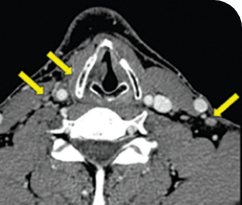

THYROID CANCER PATIENTS WITH METASTATIC DISEASE

BASELINE

AFTER 2 MONTHS OF TREATMENT

56-YEAR-OLD FEMALE WITH MULTIPLE METASTASES3

PATIENT CASE:

METASTATIC, RAIa-REFRACTORY,

PAPILLARY THYROID CANCER1

- 56-year-old female with PTCa that had metastasized to multiple sites, including the brain

- Progression after first- and second-line systemic treatment

- PRa after 4 weeks on VITRAKVI® (larotrectinib); CRa after 8 weeks

- At last assessment, complete response was sustained over an 11-month period

Clinical presentation1

- Patient was assessed to have metastatic, rapidly progressive, RAl-refractory PTC based on imaging that revealed multiple metastatic sites, including the neck, mediastinum, lung, scalp, and bones

- Biopsy of a scalp lesion helped to confirm the PTC metastasis

- Metastases to the brain and liver were observed after progression on systemic treatments

Prior treatments and outcomes1

- Prior treatments included surgery, RAI, a combination of zoledronic acid and sorafenib, external beam radiotherapy, and then lenvatinib

Testing1

- With no further treatment options, the decision was made to perform genomic testing. NGSa testing was performed on a scalp biopsy and revealed an ETV6a-NTRK3a gene fusion. The scalp biopsy had been performed 1 year earlier.

VITRAKVI treatment1

- VITRAKVI 100 mg twice daily orally

Response to VITRAKVI1

- After 8 weeks on VITRAKVI, all target lesions had disappeared, demonstrating a complete response

- The complete response was sustained over 11 months of treatment with VITRAKVI

- Patient experienced Grade 1 fatigue and mild hepatic enzyme elevation

Response in primary and metastatic lesions1

MRIa imagery of the lungs. Arrow indicates large target lesion in left lung.1

SCAN 1: LUNG

MRIa imagery of the brain. Arrow indicates large target lesion in left lung.1